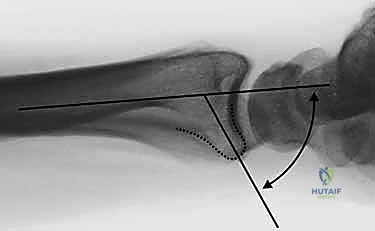

- تشوه مرئي (Deformity): في حالات الانزياح الكبير، قد يبدو الرسغ معوجاً أو منحنياً بشكل غير طبيعي. يُعرف التشوه الكلاسيكي باسم "تشوه شوكة العشاء" (Dinner Fork Deformity)، حيث ينزاح الرسغ للخلف.

- الأشعة السينية (X-rays):

هي الخطوة الأولى لتقييم الكسر. يتم أخذ صور من زوايا متعددة (أمامية خلفية، جانبية، ومائلة) لتحديد موقع الكسر الأساسي ودرجة الانزياح والتقصير في عظم الكعبرة.